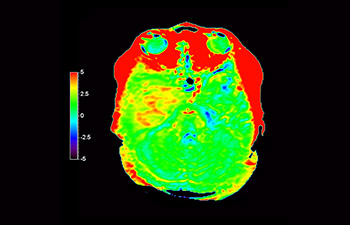

3D APT (Amide Proton Transfer) is a unique, contrast-free, brain MR imaging method addressing the need for more confident diagnosis in neuro oncology. 3D APT uses the presence of endogenous cellular proteins, to produce an MR signal that directly correlates with cell proliferation, a marker of tumoral activity. 3D APT can support trained medical professionals in differentiating low grade from high grade gliomas and, in differentiating tumor progression from treatment effect1.

3D T1w TFE 3D APT

Glioblastoma recurrence

Brain imaging for glioblastoma recurrence

with 3D APT